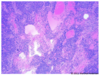

Parotid Gland

Parotid Gland

Parotid Gland

Parotid Gland